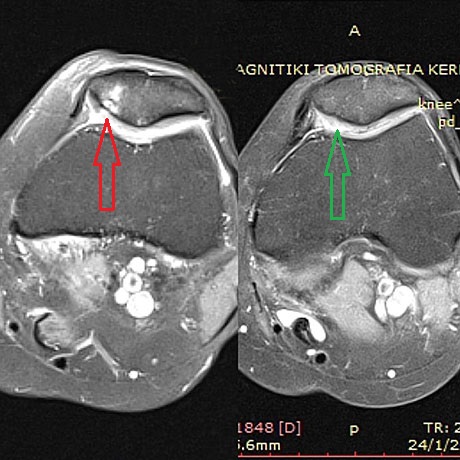

Woman 59 years old with severe damage of the patellar articular cartilage. Autologous bone marrow stem cells with collagen (AMIC technique), before and two years postop

The same patient.